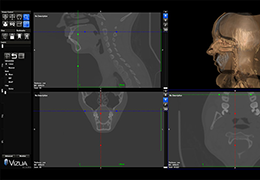

ANYTHINK 经导管主动脉瓣膜置换术分析系统